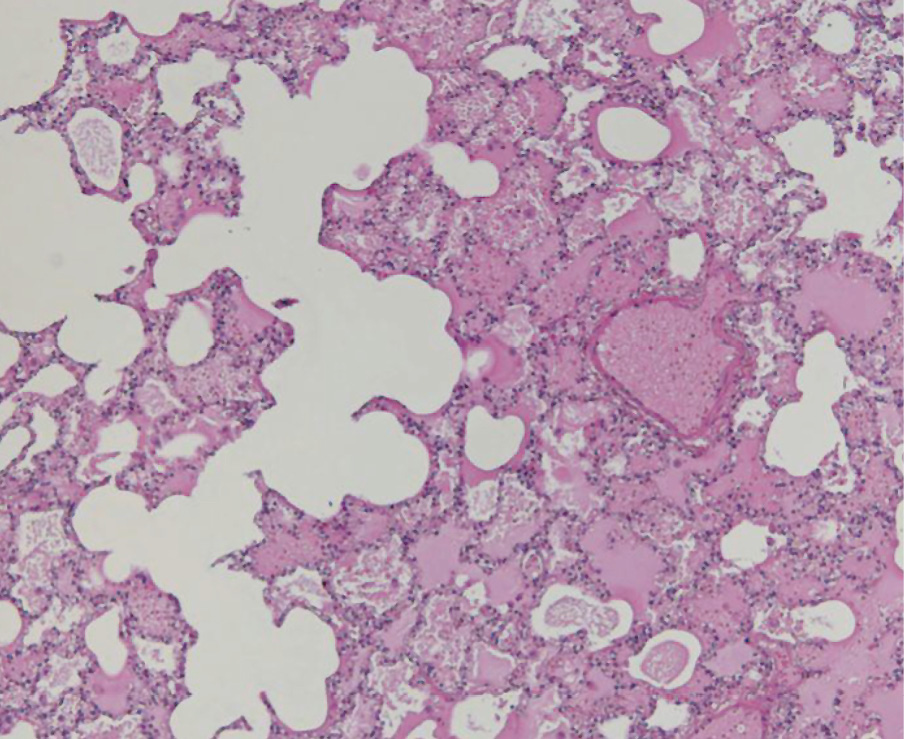

Emphysema aquosum is frequently highlighted in forensic literature as an important drowning sign, and accompanying lung changes must be correctly interpreted [15]. As a result of the airways closing during expiration, increased phlegm production and foam creation cause the hyperinflated lung as a valve mechanism. These mechanisms create the image of ballooned lungs filling the pleural cavities and reaching over the pericardium with their edges (Fig. 5). Imprints of the ribs on the lung surface can often be seen. Histologically, the overinflated lungs present flattened and ruptured interalveolar septa surrounding blister alveolar cavities. In addition, anemic and normally perfused areas alternate in the lungs, whereas the alveoli–capillary membrane is damaged. The severity of this injury is proportional to the duration of the drowning process. Other signs of pulmonary hyperinflation include washed-out rhexis bleeding under the pleura, called Paltauf’s spot [15]. Paltauf’s spot refers to bleeding spots caused by increased pressure, leading to the rupture of the alveolar walls, mostly found on the anterior surfaces and borders of the lung, and can be found in the subpleural if there has been further leakage or rupture [7].

Fig. 5. Emphysema aquosum and intra-alveolar edema [8].